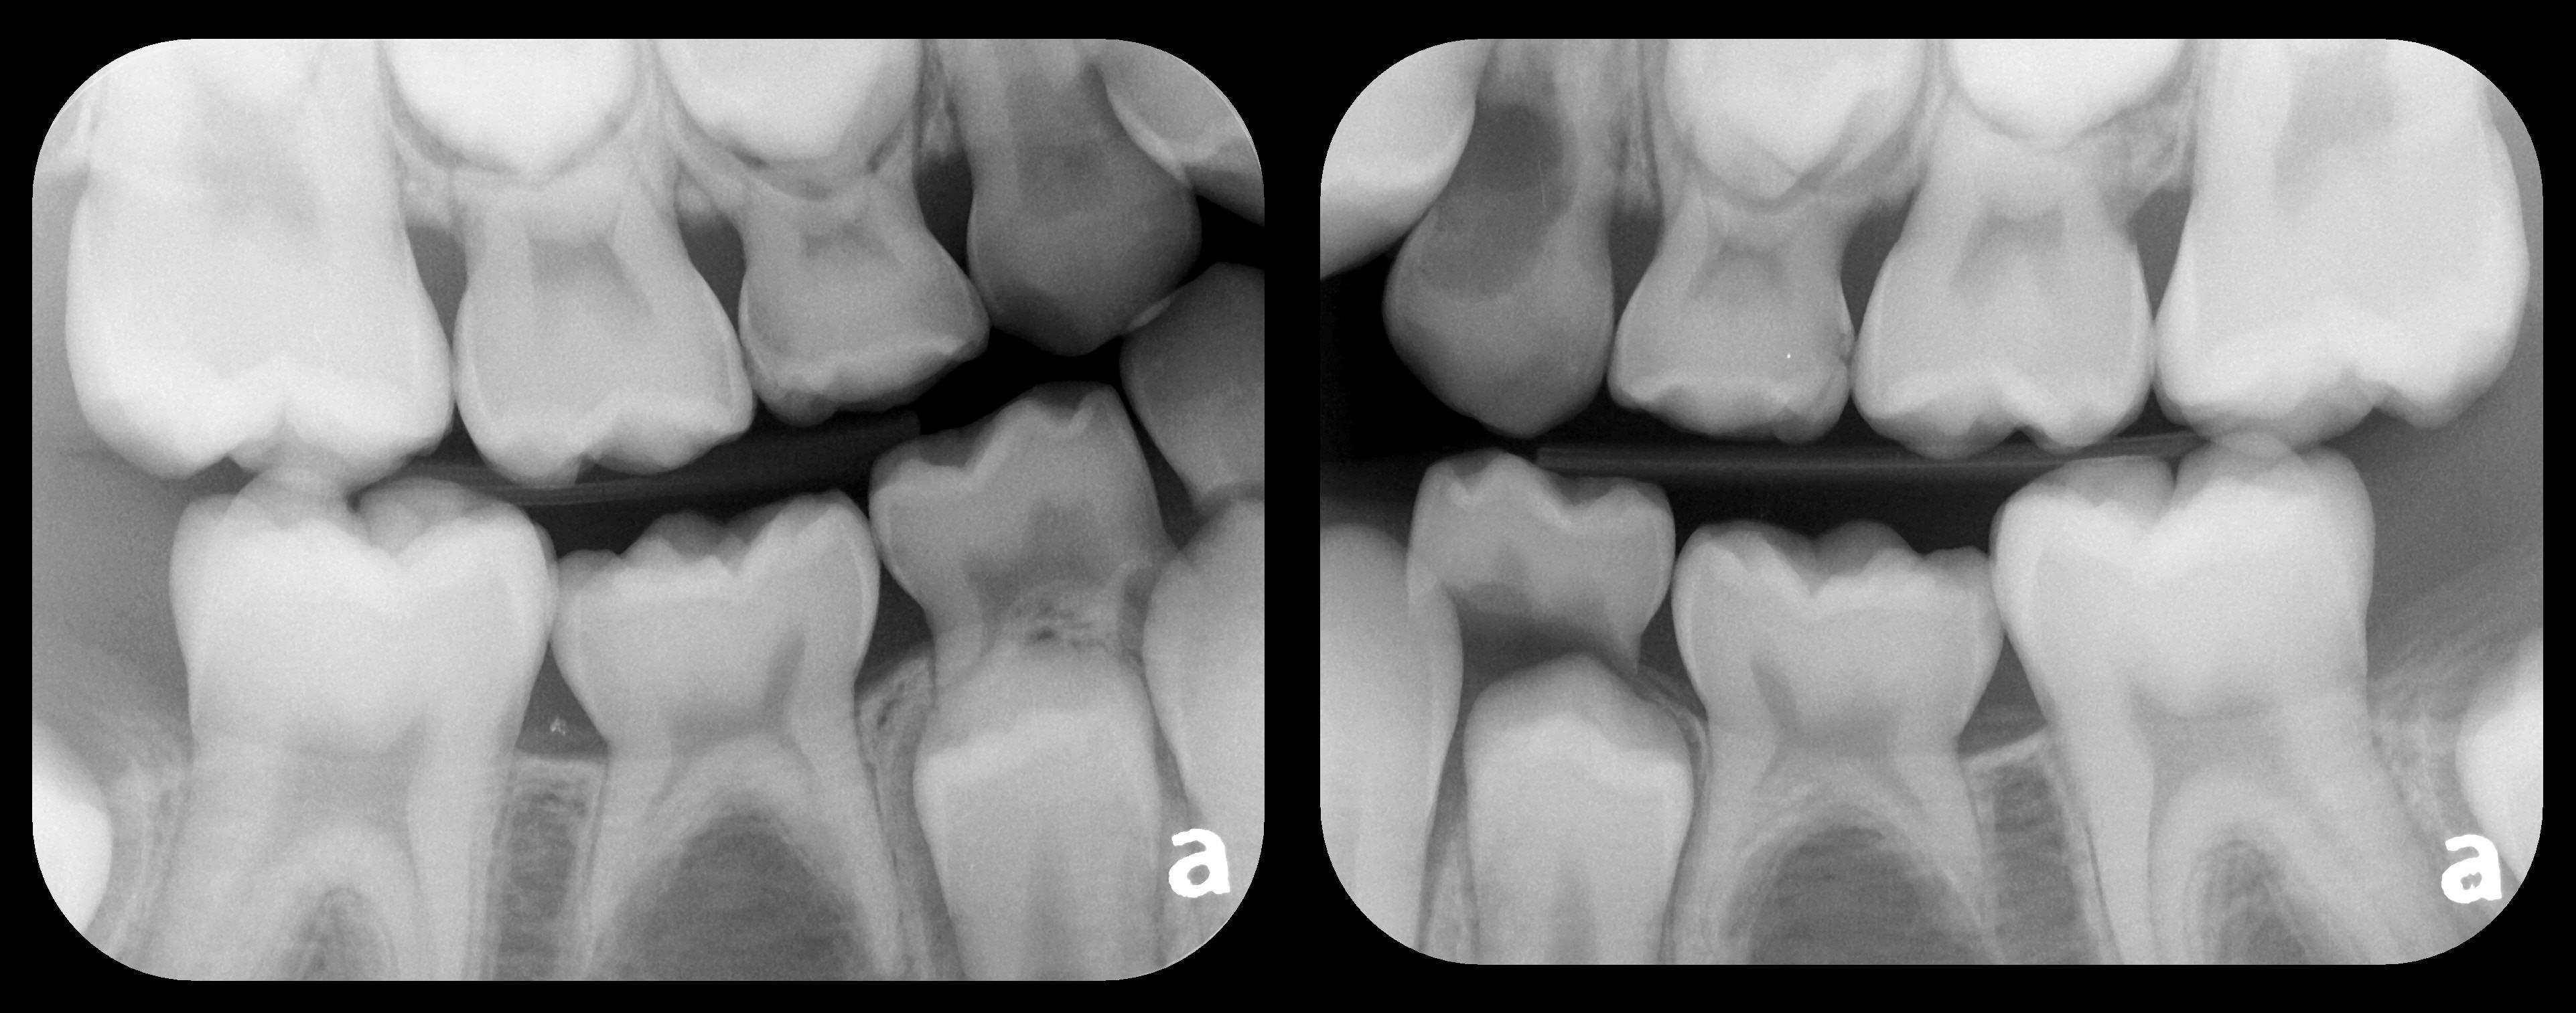

There are two specific types of DIDR sensor systems available to dentists in the marketplace: the hard-wired (HW) sensor and the photostimulable phosphor (PSP) sensor,1,2 also commonly known as phosphor "plates." A desirable feature common to both modalities is the ability to expose either bitewing (BW) or PA radiographic images. The BW radiograph (Figure 1) is usually considered more appropriate for caries detection, whereas the PA (Figure 2) is diagnostic for several different anatomic and pathologic issues.7

Fig 1. Left: Representative PSP BW radiograph with multiple restorative materials of varying radiographic densities. Tooth No. 31 demonstrates deep

caries on mesial aspect beneath the restorative. Radiolucency of carious lesion results from the low relative density of caries compared with healthy

tooth structure. Right: PSP BW radiograph optimized for view of multiple interproximal carious lesions.

Figure 1